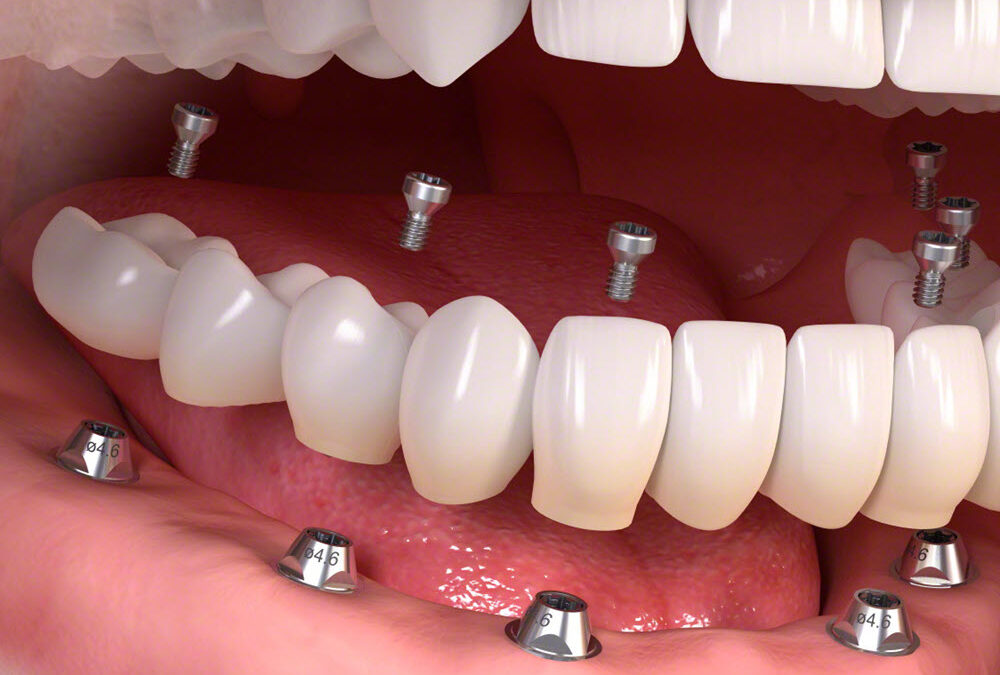

A fogászati implantátumok hosszú távú sikeressége nemcsak a beültetés minőségén, hanem több páciensspecifikus tényezőn is múlik – ilyen például a csont stabilitása, a dohányzás, korábbi fogágybetegség, vagy az implantátum pontos elhelyezése. Egy nemrégiben készült tanulmány azt vizsgálta, hogy a szomszédos implantátumok közötti függőleges távolság (VID) befolyásolja-e az implantátum körüli csontveszteséget és a lehetséges komplikációkat.

A kutatók a friss tanulmányban 290 páciens adatait elemezték, akiknél 376, egymás mellé beültetett, hátsó régióba szánt egytagú implantátum került beültetésre. A vizsgálat során két csoportot különítettek el aszerint, hogy a platformok közötti magasságkülönbség kevesebb mint 2 mm volt-e, vagy elérte/átlépte a 2 mm-t. Ezen kívül a vízszintes távolság (HID) hatását is vizsgálták.

Az implantációkat előzetes digitális tervezés alapján, standard sebészi eljárásokkal végezték, és ha szükséges volt, csontpótlást is alkalmaztak. A gyógyulási idő 3–6 hónap volt, ezt követően éves kontrollvizsgálatokat végeztek. A kiértékeléshez korszerű képalkotó technikákat – CBCT-t és röntgenfelvételeket – használtak, a mérések egységesítéséhez pedig az ImageJ szoftvert vették igénybe.

Az implantátumok túlélési aránya mindkét csoportban hasonlóan magas volt (93,2% és 96,8%), a különbség azonban statisztikailag nem bizonyult jelentősnek. Azoknál az eseteknél, ahol az implantátumok közötti függőleges távolság kisebb volt, gyakrabban fordult elő jelentősebb – 0,5 mm-nél nagyobb – csontveszteség, főként az implantátum körüli perem- és csontgerinc területeken.

A szövődmények kialakulását nem elsősorban az implantátumok közti távolság befolyásolta, hanem más tényezők, például ha a korona alatt nem lehetett hozzáférni a rögzítőcsavarhoz, ha az implantátum az alsó állcsontba került, vagy ha a hátsó implantátumot túl magasan helyezték el.

Pozitív hatást mutattak azok az esetek, ahol hosszabb implantátumokat alkalmaztak, az implantátumokat párhuzamosan helyezték be, illetve olyan koronát használtak, amelynél a rögzítőcsavar szükség esetén elérhető maradt.

A vizsgálat egyik fő üzenete, hogy sem a vertikális, sem a horizontális távolság nem befolyásolta érdemben az implantátum hosszú távú megtartását vagy a csontvesztést. Ez azt jelenti, hogy bizonyos esetekben nincs szükség mélyebbre ültetett implantátumra vagy kiterjedt csontpótlásra, még ha magasságbeli eltérés is van a beültetett elemek között. Ez egyszerűbb és költséghatékonyabb kezeléstervezést is lehetővé tehet, különösen egyenetlen csontállomány esetén.